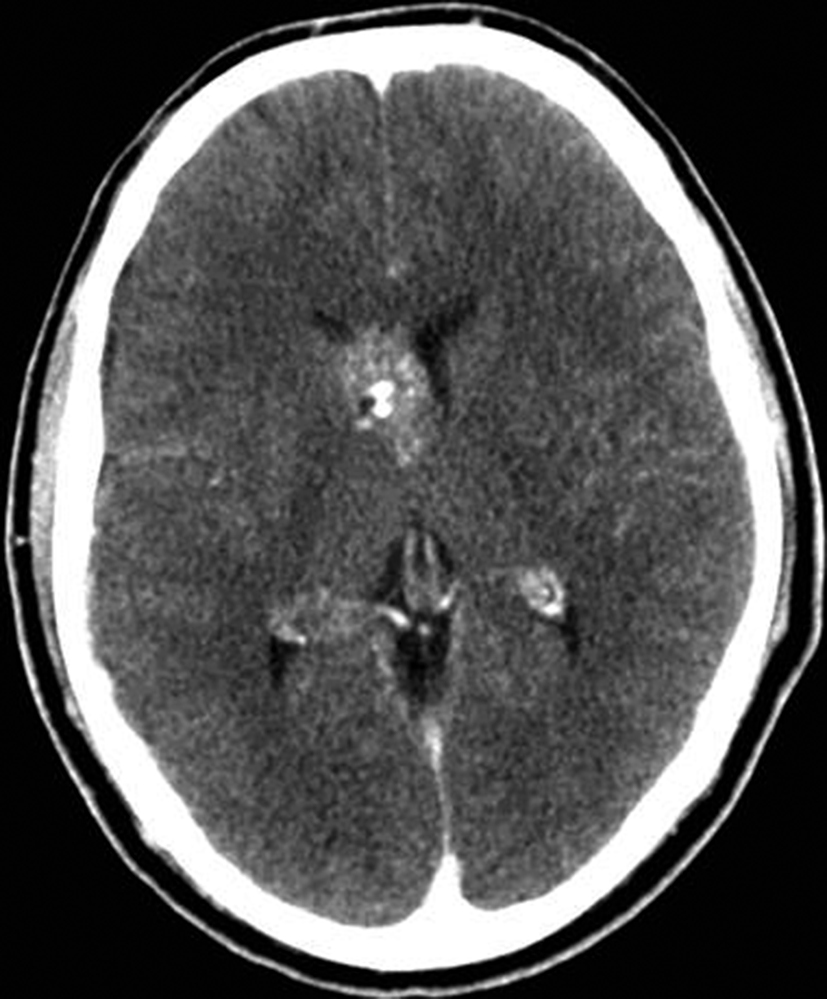

Se presenta el caso clínico de un paciente de sexo masculino, de 36 años de edad, sin antecedentes personales a destacar. Consulta por cefalea holocraneana de larga data, sin déficit neurológico y examen físico normal. Dada la clínica del paciente se realiza una tomografía computada de cráneo sin contraste intravenoso que identifica una lesión bien definida espontáneamente hiperdensa, heterogénea con calcificaciones puntiformes localizada en el asta frontal del ventrículo lateral derecho. No hay edema peri-lesional, efecto de masa ni hidrocefalia (Figura 1- A). Debido a los hallazgos se decide administrar contraste intravenoso, no evidenciándose realce significativo de la lesión (Figura 1- B).

Se efectúa un control imagenológico al año del diagnóstico mediante una TC sin y con contraste (Figura 5 – A y B), donde se evidencia la lesión sin cambios significativos en cuanto a su tamaño y características.

Figura 1

a) TC sin contraste. Lesión

intraventricular hiperdensa,

heterogénea con pequeñas

calcificaciones.

a) TC con contraste. No se

identifica realce significativo

de la lesión.

Figura 5

a y b) Cortes axiales de TC sin y con contraste intravenoso. Control

tomográfico al año

del estudio inicial, no

se observan cambios

significativos de la lesión.

En la TC sin contraste, el cavernoma es una lesión bien

definida e hiperdensa. El aumento de la densidad puede

tener un aspecto punteado, que puede representar calcio,

sangre o una combinación de ambos y el realce tras

la administración de contraste varía de ninguno a muy

intenso (1,3,5).